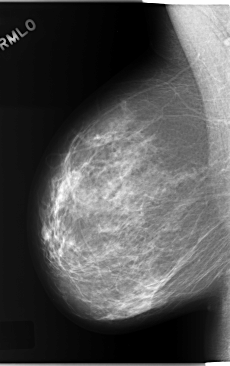

C_0207_1.RIGHT_MLO

RIGHT_CC LINES 6008 PIXELS_PER_LINE 3848 BITS_PER_PIXEL 12 RESOLUTION 50 NON_OVERLAY

RIGHT_MLO LINES 5856 PIXELS_PER_LINE 3672 BITS_PER_PIXEL 12 RESOLUTION 50 NON_OVERLAY